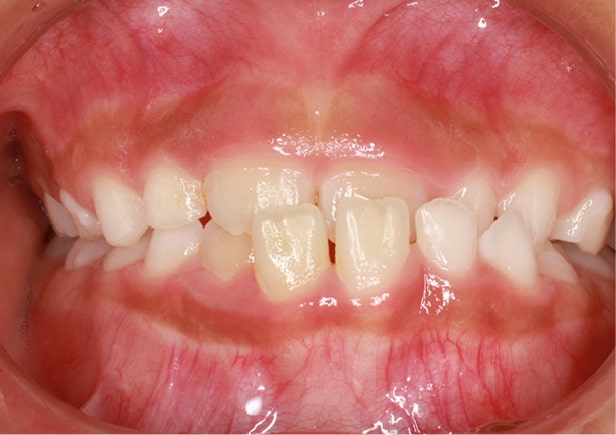

• 症例1

矯正bofore

矯正after

矯正種類 マウスピース矯正

症例 すきっ歯

治療期間 令和5年9月〜令和6年3月 6ヶ月

性別/年代 男性/20歳9ヶ月

治療費 上下顎 : 280,000円(税別)

治療のデメリット

• ・保険適用がされないので治療が高額になる

• ・後もどり、再発と再治療の可能性がある

• ・歯肉(歯ぐき)の退縮の可能性がある

• ・歯根(歯の根っこ)の吸収の可能性がある

• ・歯の失活の可能性がある

担当医師

コメント

短期間でしっかり空隙も無くなりました。

上顎だけの治療でしたが、その過程で下顎の叢生(でこぼこ)も綺麗になった好症例です。